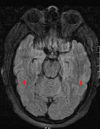

Figure 1. Magnetic resonance imaging (MRI) of the brain

Normal brain MRI with no abnormal leptomeningeal or intraparenchymal enhancement (red arrows). No hemorrhage, mass, or acute infarct seen.